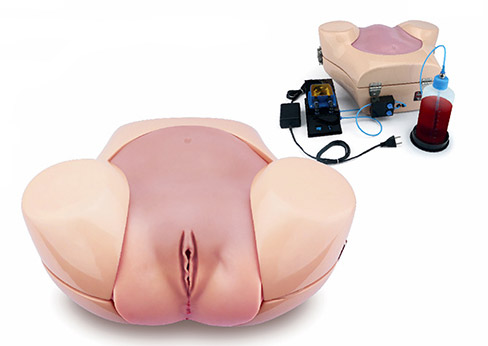

ETH Artıfıcıal Uterus

Dünyanın önde gelen jinekologlarının gözlemlerine göre tasarlanan yapay uterusun patolojileri, vajinal histeroskopide eğitim için, tortuoz serviksin değerlendirilmesi, tanı muayeneleri, biyopsi gibi işlemler, yabancı vücut yapılarının çıkarılması, myomlar, polipler, uterin yanlış biçimlerinin değerlendirilmesi ve düzeltilmesi ve daha birçok işlemin gerçeklemesini sağlar.

Bazı modellerde kanama da gerçeklenebilmektedir.

Histeroskopi eğitim simülatörü ile birlikte kullanılmaktadır.